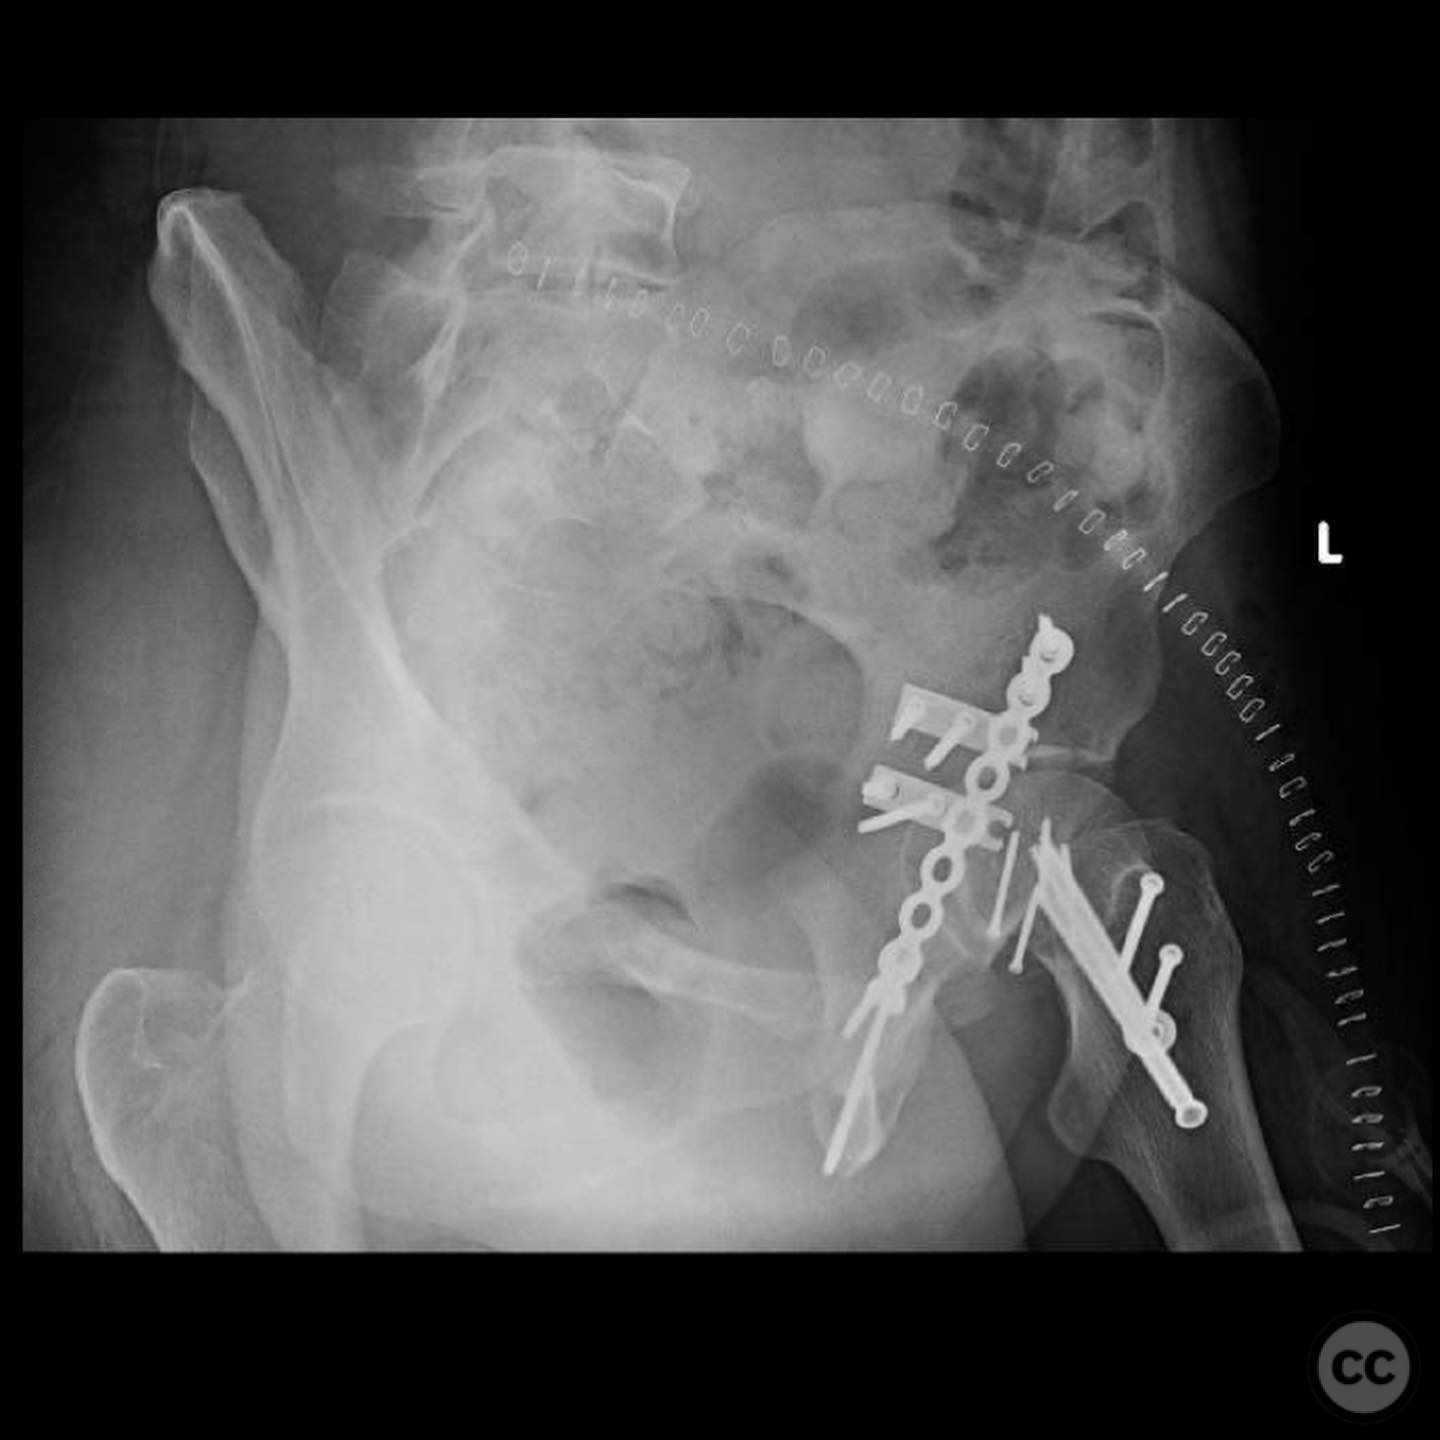

The femoral head defect required meticulous reconstruction using a femoral head allograft to restore its round shape. The posterior wall instability was addressed with spring plates and three suture anchors to reattach the capsulolabral complex. The reconstruction aimed to achieve a stable and congruent hip joint.

Postoperative protocol:   Postoperative rehabilitation included non-weight bearing on the affected limb for 6 weeks, followed by gradual weight-bearing as tolerated. Range of motion exercises were initiated early to prevent stiffness.

Orthopaedic implants used:   Femoral head allograft, spring plates, suture anchors.